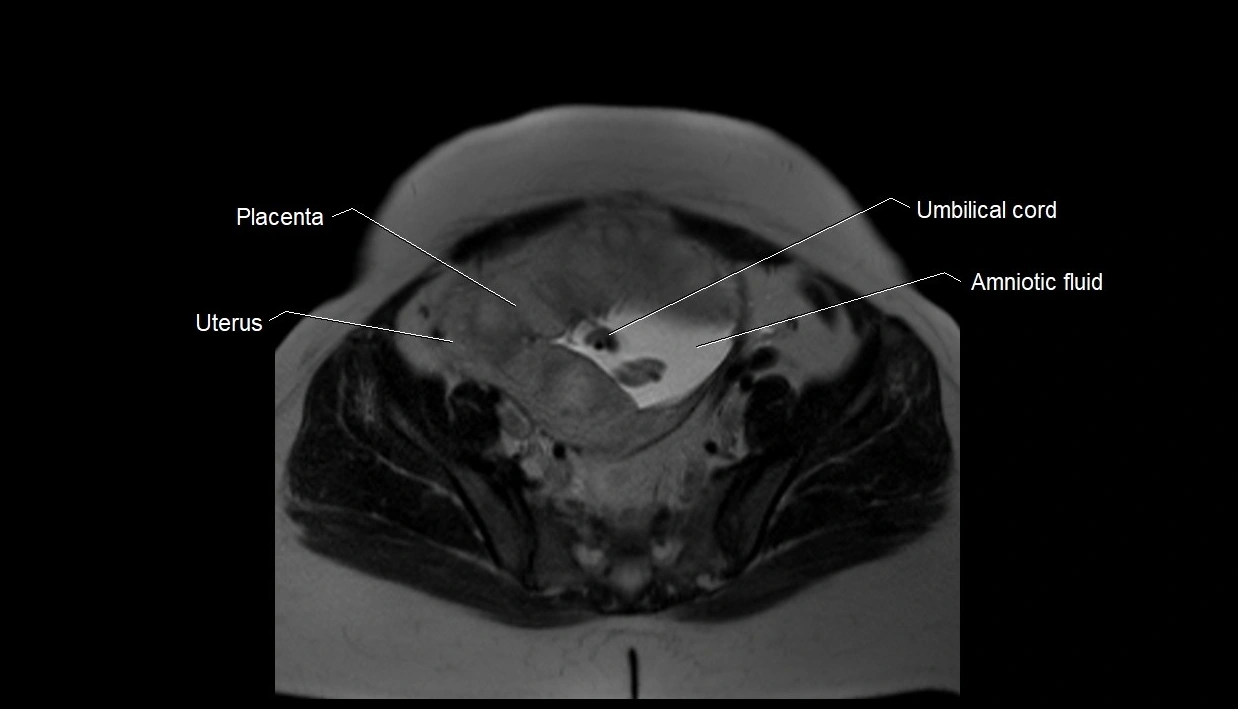

MRI Appearance

T2 HASTE (T2 GRE):

• Amniotic fluid shows very bright hyperintense signal

• Provides natural contrast against fetus and placenta

• Small particles (vernix) may appear as scattered hypointense foci within bright fluid